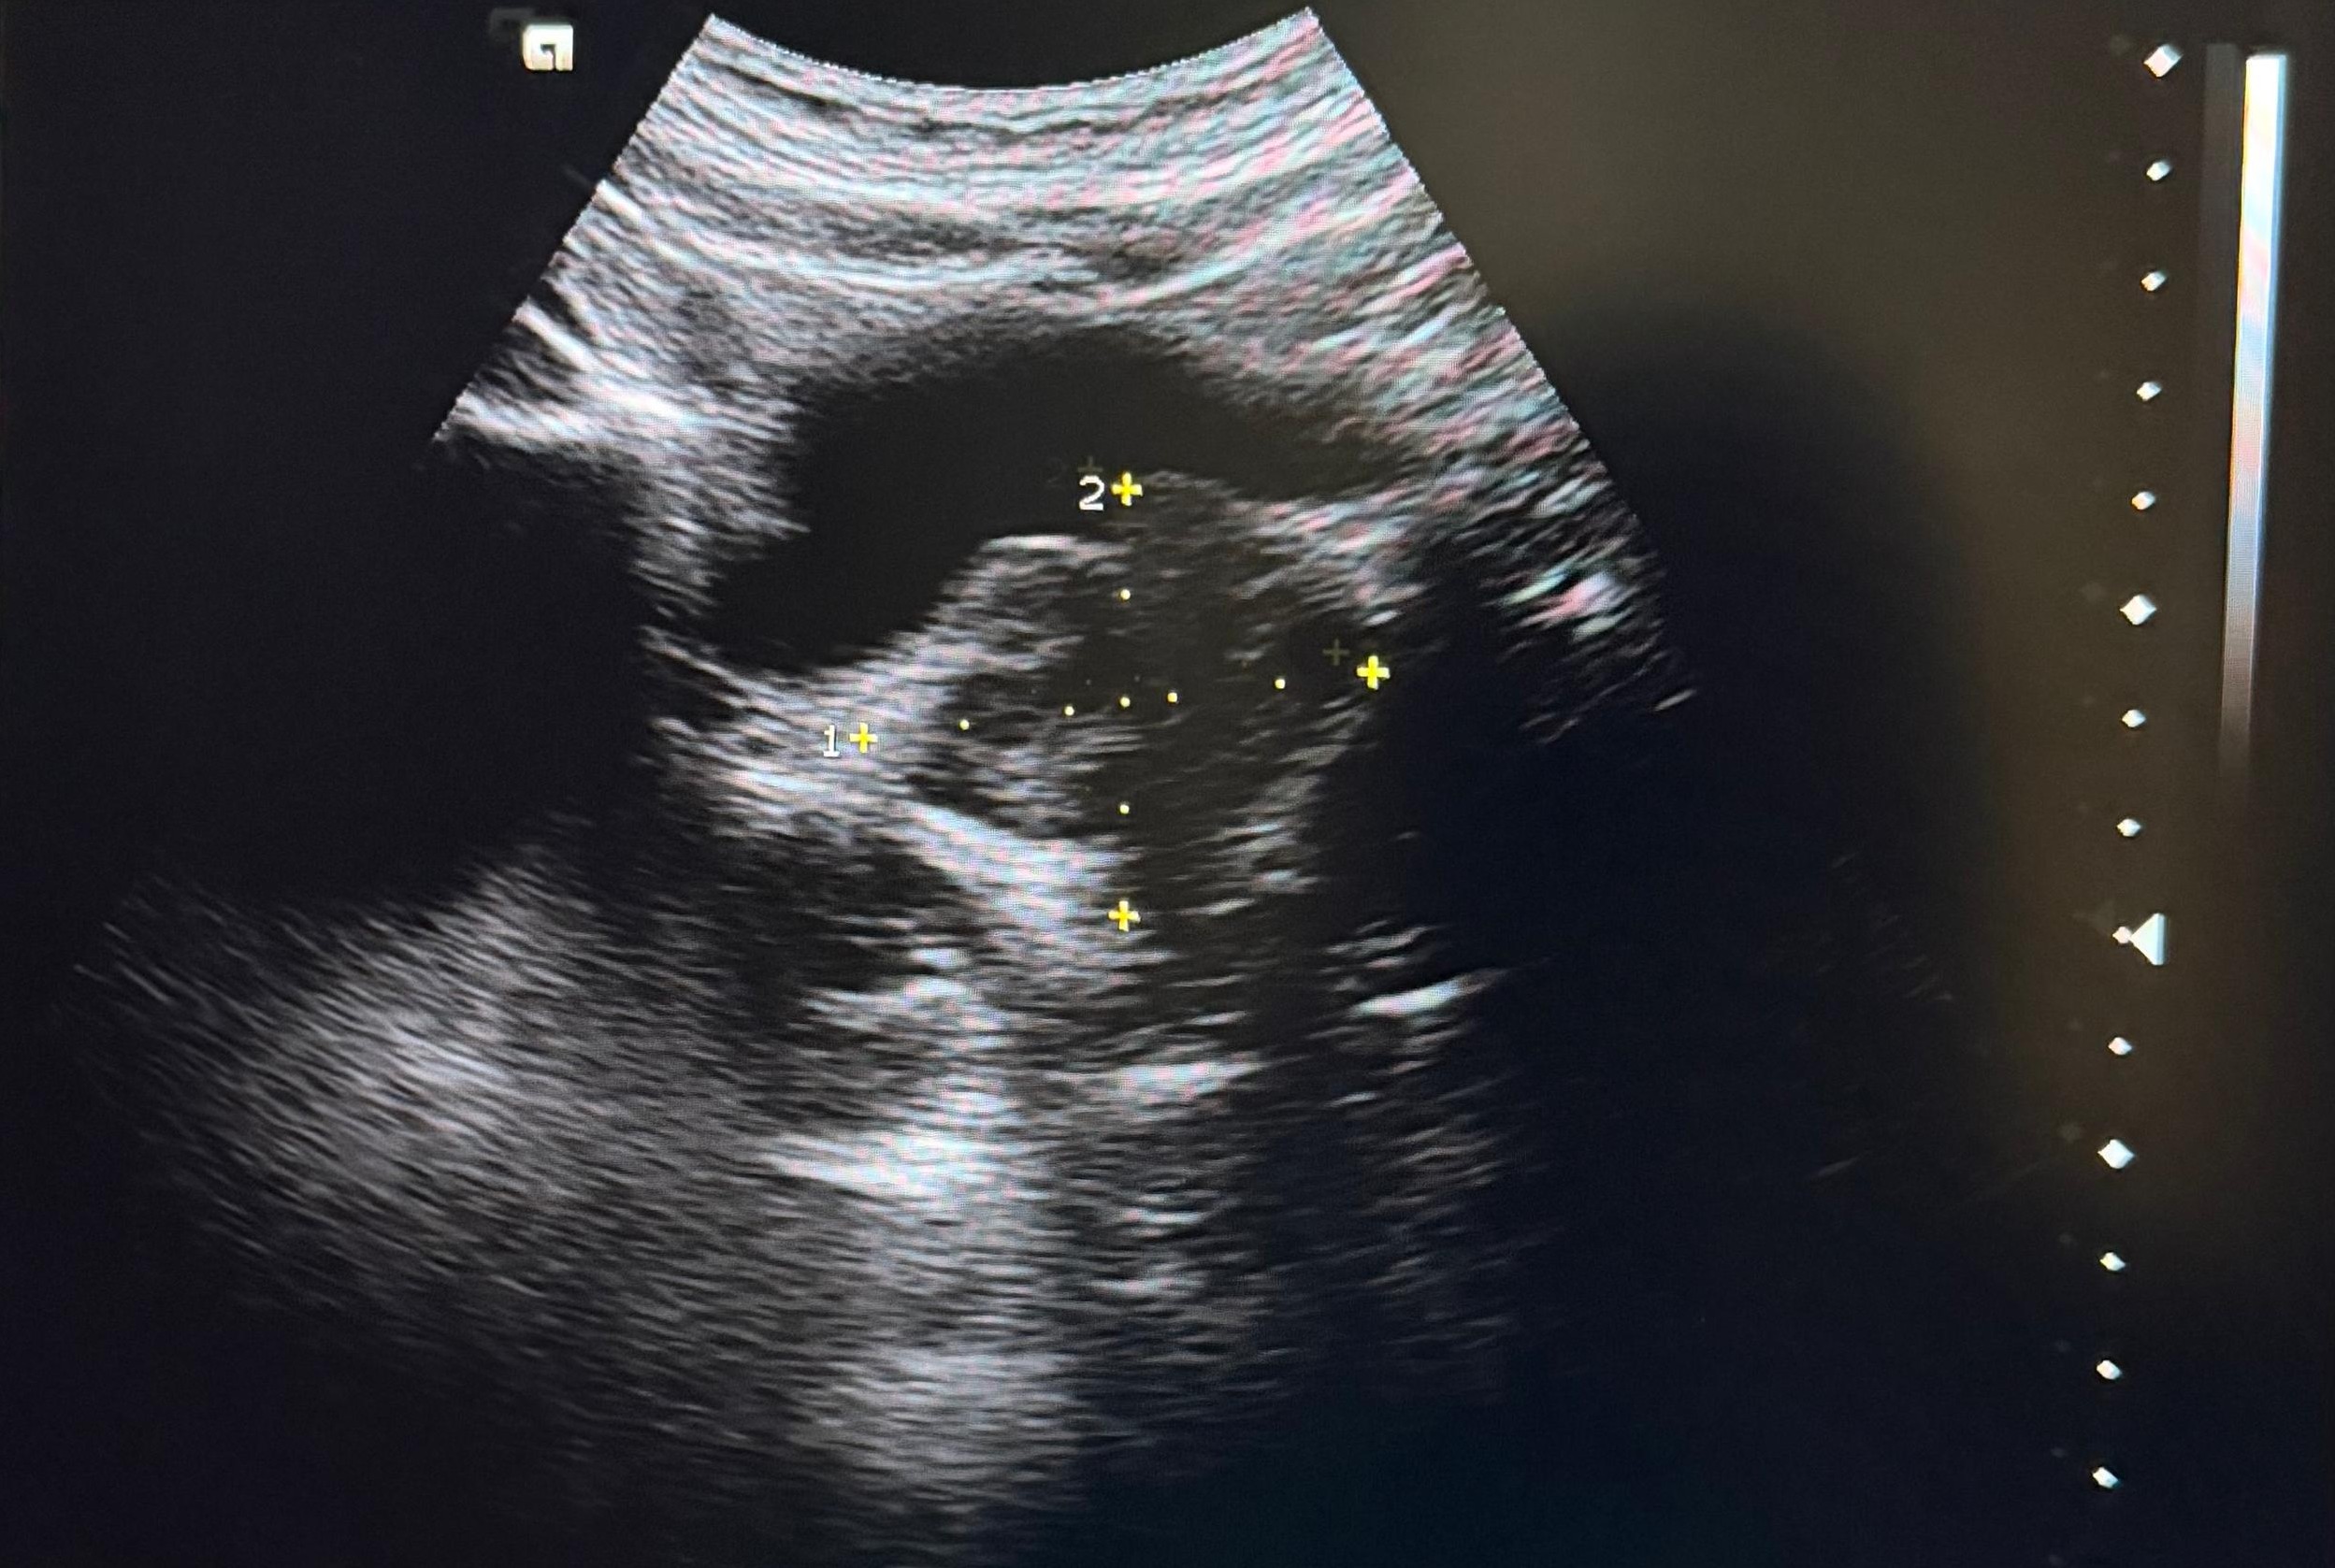

Hallazgos ecográficos

Se realiza ecografía abdominopélvica donde se visualiza vejiga sin alteraciones, próstata aumentada de tamaño con un volumen estimado de 59 cc. Como hallazgo incidental se objetivan ambos riñones aumentados de tamaño con varios quistes.

Juicio clínico: HBP y hallazgos compatibles con quistes simples vs poliquistosis renal.